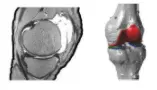

关节有限元分析人体关节尤其是大腿骨两端的髋关节以及膝关节,一直以来也是病症多发部位,应用CAE技术模拟人体关节力学结构是一种有效的方法。上肢的肘关节、腕关节的研究常常与骨折以及其他骨骼创伤性疾病的应力分析联系在一起。

而在髋关节方面,有限元分析较为广泛地应用于全髋关节置换的研究,分析全髋关节置换术前术后髋关节应力的分布情况,而且还可对骨水泥残余应力的细致分析和假体设计进行研究。对于膝关节分析来说,建立一个完整的三维有限元计算模型,不仅可以了解各部位的应力分布和工作原理,还有助于人工膝关节置换的合理设计。

图 | 膝关节半月板模拟分析